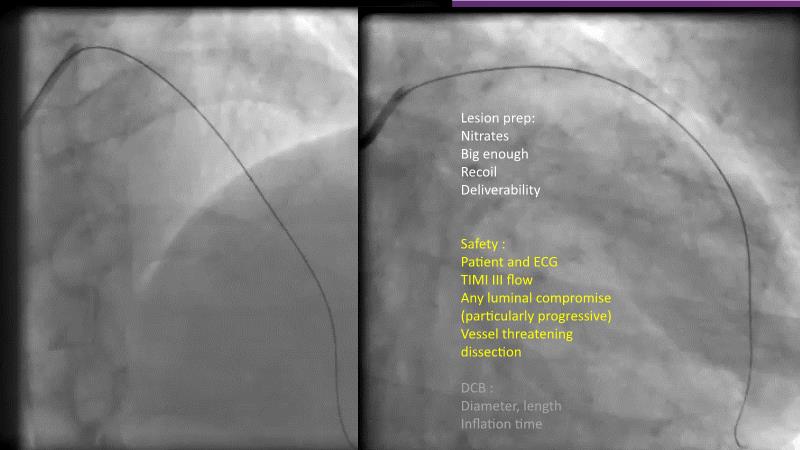

DES and DCB, can these two technologies be complementary for the treatment of the same patient? What are the advantages and how to proceed? You will know everything by watching this presentation based on concrete cases.